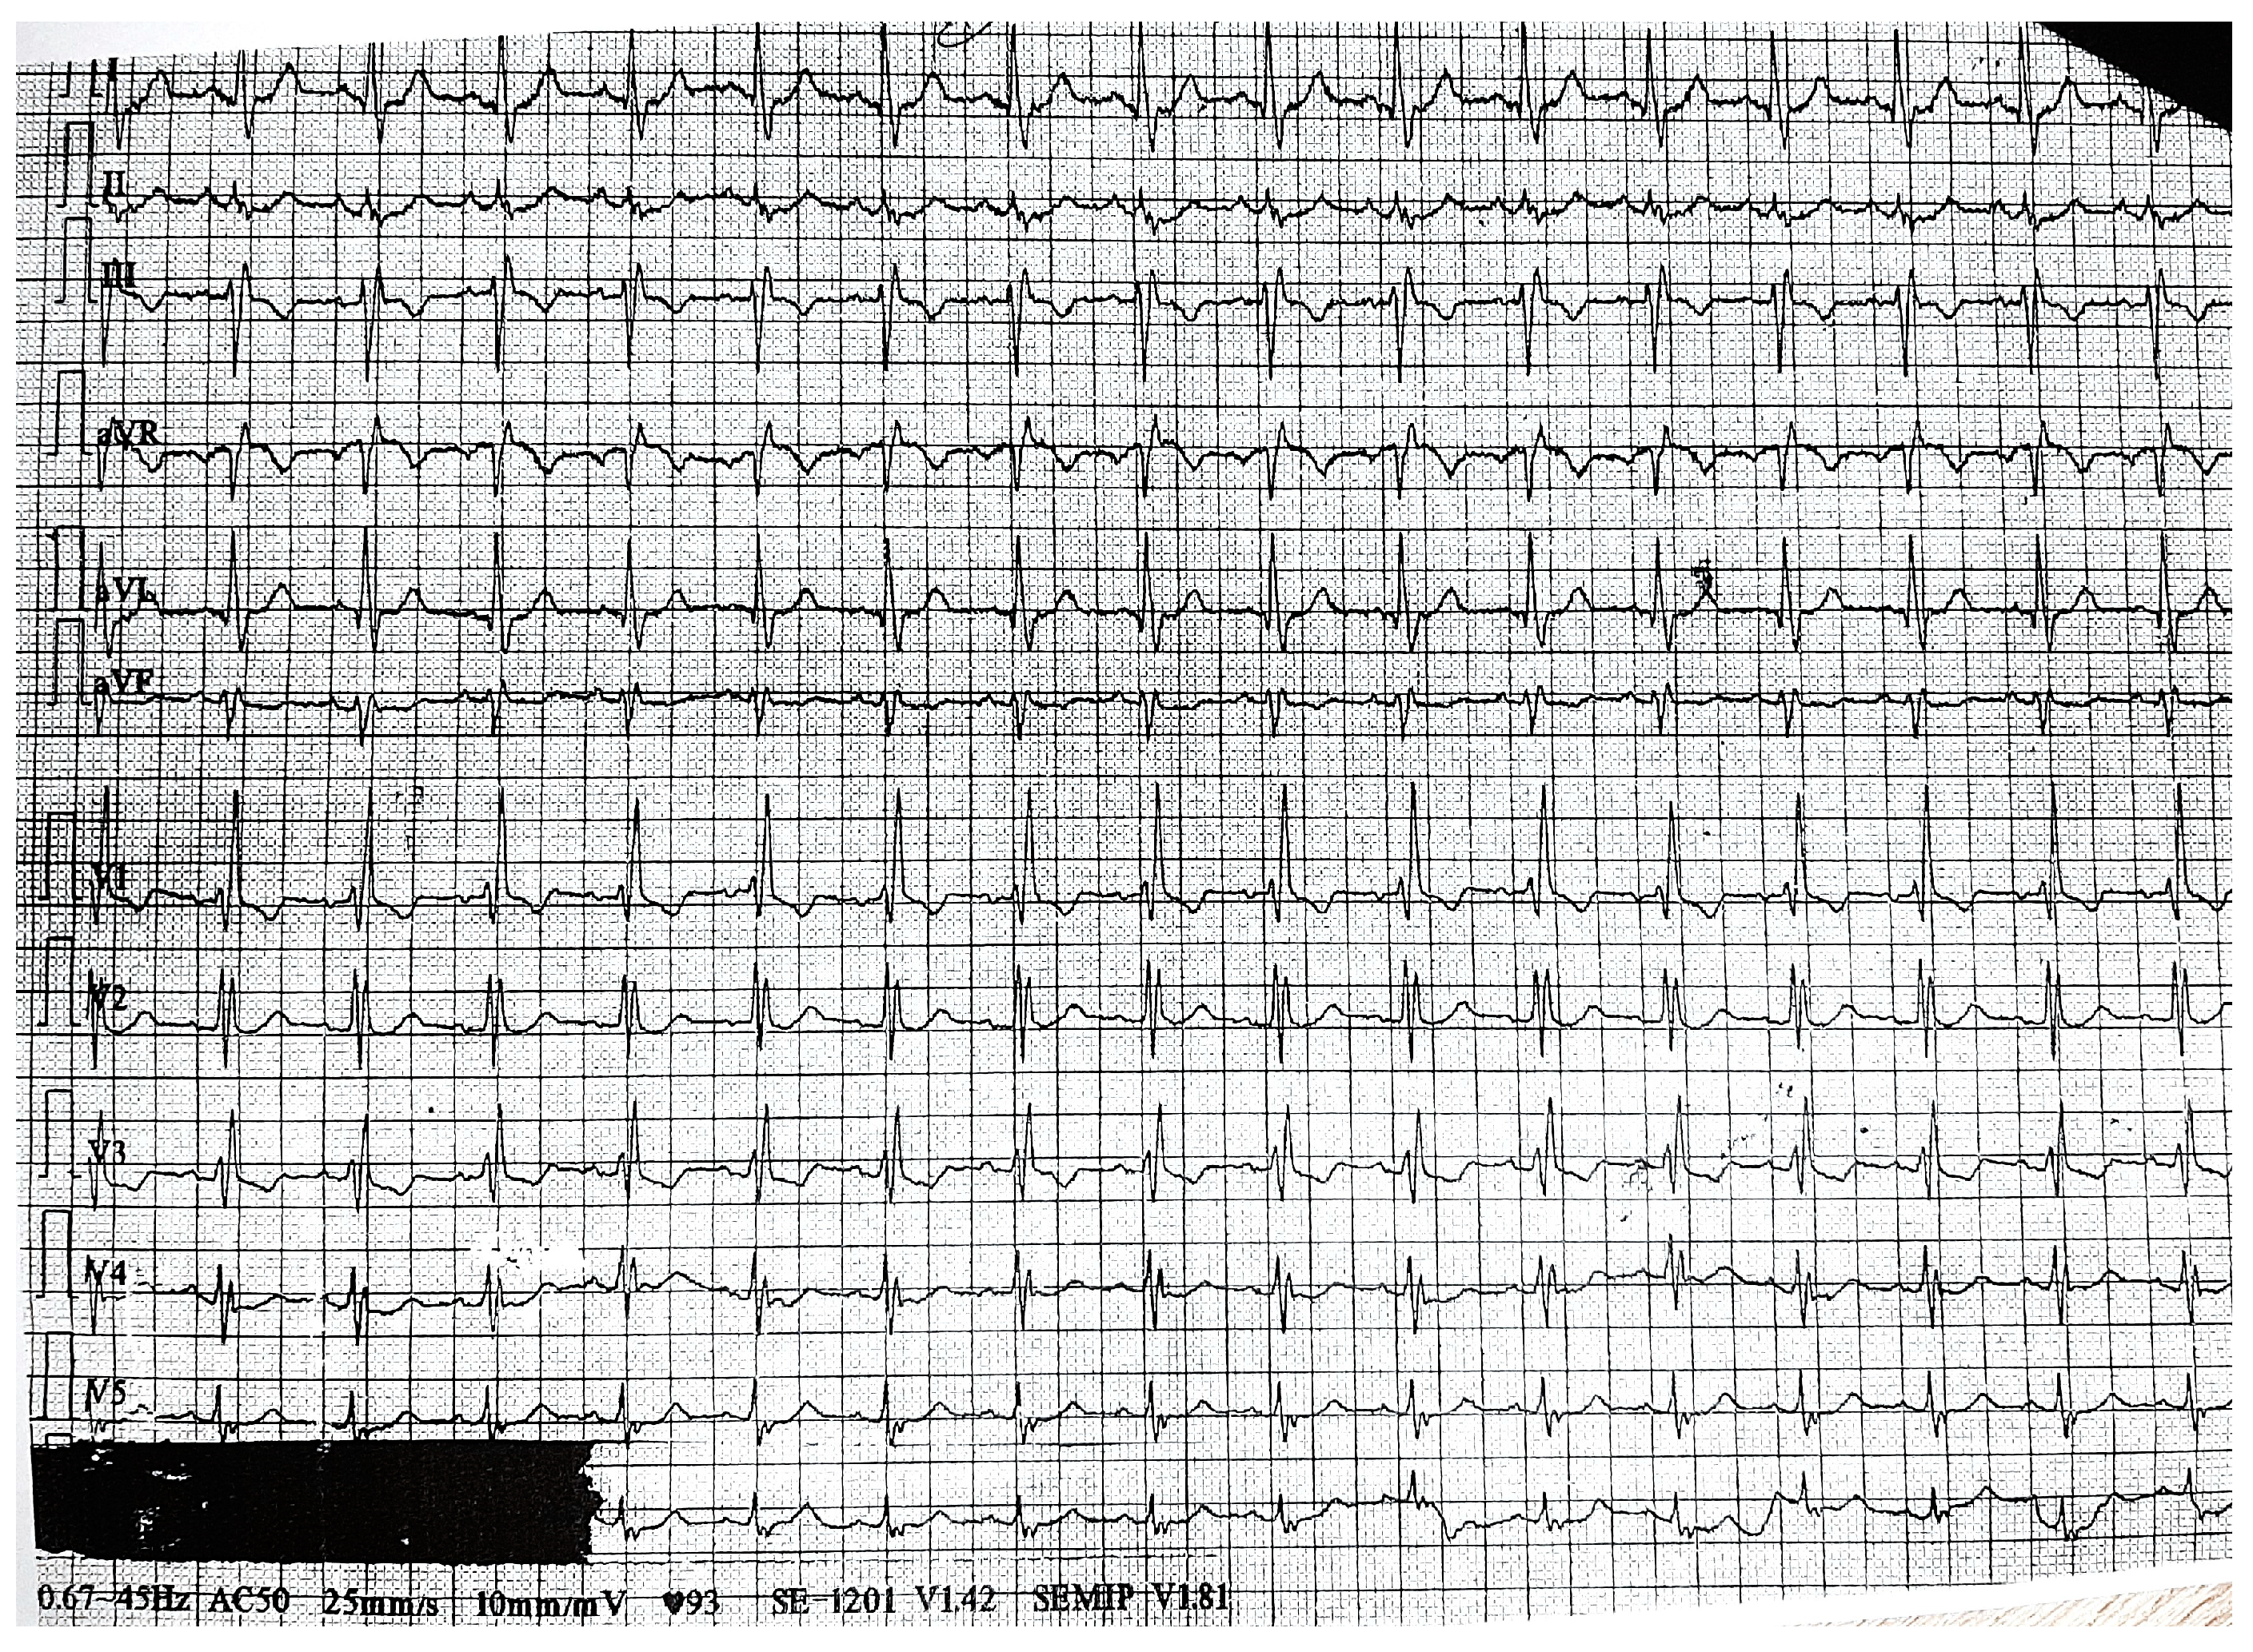

2. Case Presentation